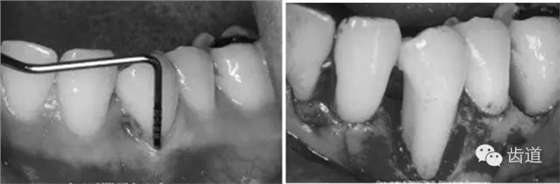

5、膜材料的邊緣位置和固位

原則是生物膜能充分覆蓋病損區(qū)。冠方緊鄰釉牙骨質(zhì)界,根方伸展至骨邊緣下2~3mm,保證在組織愈合過程中能確切阻止口腔上皮和牙齦結(jié)締組織與牙根面接觸。

當(dāng)生物膜放置就位后,為防止受齦瓣的擠壓而移位后影響療效,應(yīng)用細(xì)線穿過生物膜的上部邊緣使之緊緊環(huán)抱牙齒,并采用懸吊縫合將其固定于牙面上。